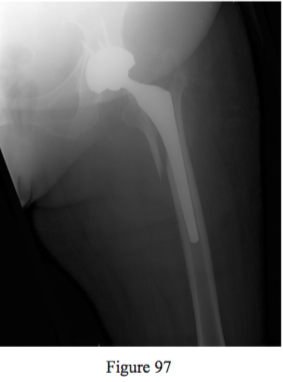

Question 97

Figure 97 reveals a fracture sustained by a 60-year-old man 5 weeks after he underwent total hip arthroplasty. What is the most appropriate way to treat this fracture?

PREFERRED RESPONSE: 4